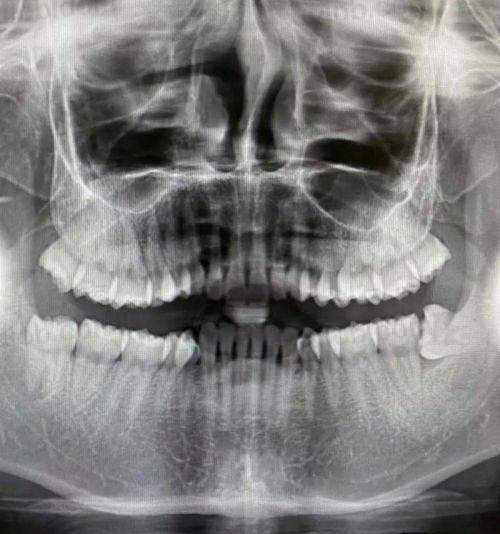

北京雅仕口腔配备了精良的口腔检查和治疗设备。这些设备不仅能提高检查的正确性,还能为治疗提供有力的支持。例如,精良的口腔全景机可以清晰地显示牙齿和颌骨的情况,帮助医生更正确地诊断病情。www.xiujob.com在治疗过程中,精良的治疗设备可以提高治疗效率,减少患者的痛苦。